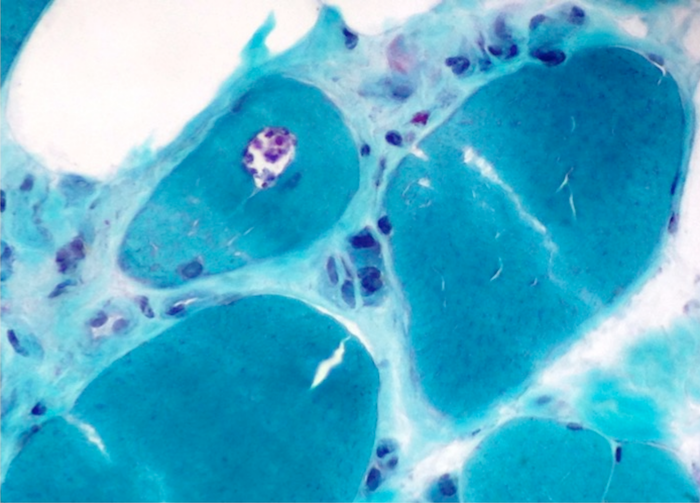

- The Gomori Trichrome stain shows "rimmed vacuoles", although the extent of myofibers having classic rimmed vacuoles varies (Dubowitz: Muscle Biopsy: A Practical Approach, 2013, 4th Edition)

- The vacuoles disrupt the myofiber architecture and can lack NADH-TR staining (Dubowitz: Muscle Biopsy: A Practical Approach, 2013, 4th Edition)

- Gomori trichrome shows rimmed vacuoles and can show ragged red fibers in areas